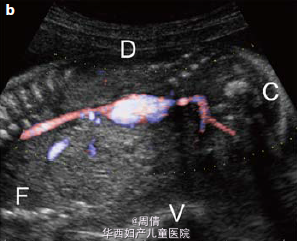

1,2.超声提示在大动脉分叉点以上的降主动脉上有一个动脉瘤,最大直径2cm 3,可见扩大的左脑室和变薄的左侧大脑实质 4,30周时胎儿MRI提示颅腔内的左侧脑室有一个增大的囊性结构